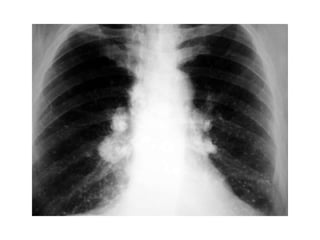

Coccidioidomicosis: Rx de tórax

• Linfadenopatía en mediastino

• Infiltrados en placas

• Con menos frecuencia (5%):

– Cavitación de paredes delgadas

– Lesiones nodulares numulares

– Derrame pleural

• En coccidioidomicosis diseminada

patron micronodular (semeja Tb miliar).

Coccidioidomicosis: Rx detórax • Linfadenopatía en mediastino • Infiltrados en placas • Con menos frecuencia (5%): – Cavitación de paredes delgadas – Lesiones nodulares numulares – Derrame pleural • En coccidioidomicosis diseminada patron micronodular (semeja Tb miliar).